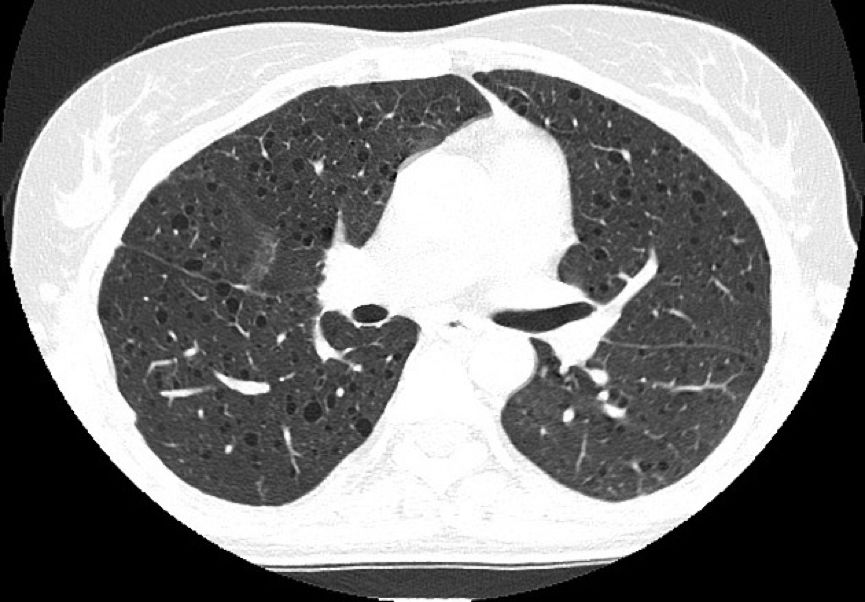

病例1:患者女性,45岁,呼吸短促,有反复气胸的病史。

病例2:患者女性,36岁,胸痛一周加重伴呼吸困难。

常规CT表现为两肺密度减低,体积增大,呈肺气肿样改变。HRCT对本病的早期诊断及病情发展的监测有重要意义,其特征性改变为两肺广泛弥漫性分布的薄壁小囊状病变,两侧对称,无上中下肺野的区别,也无中央性与周围性的分布差异。囊腔直径为2~30 mm,大多数直径小于10 mm,囊壁厚度多小于2 mm。